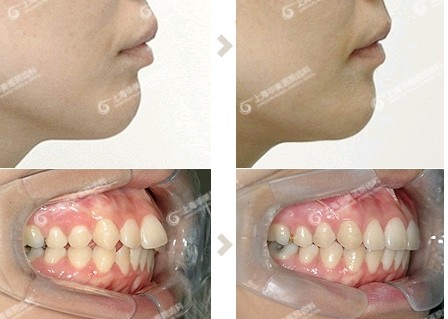

上排牙齿外突矫正 第1页 要无忧健康图库

上排牙齿突出需要做手术吗 还是矫正就 新氧 专业医美服务平台

牙齿矫正 堪比整容 牙齿矫正后完全变身 每日头条